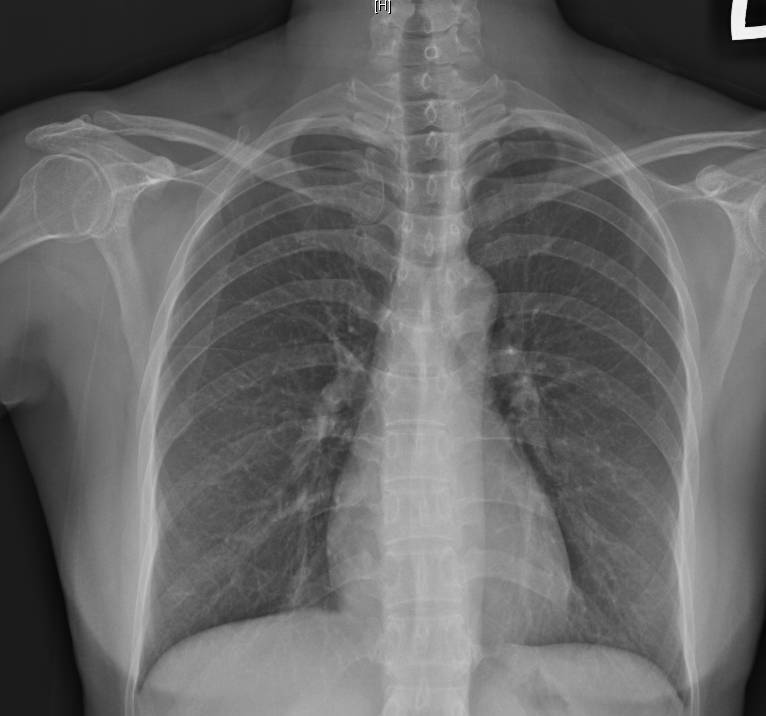

阮綜合醫院胸腔內科主任蕭惠元醫師指出:每當季節交替、日夜溫差大的時期,一些流感或風寒感冒的患者的發燒、流鼻水等症狀康復後,會有持續一段時間的乾咳,甚至持續超過3週似乎咳嗽難斷根,經X光與肺活量檢查,顯示無明顯浸潤或肺炎陰影,排除肺炎、肺癌或肺結核等重大疾病後,確診為「感染後咳嗽」;經過止咳藥物治療1週左右可痊癒。